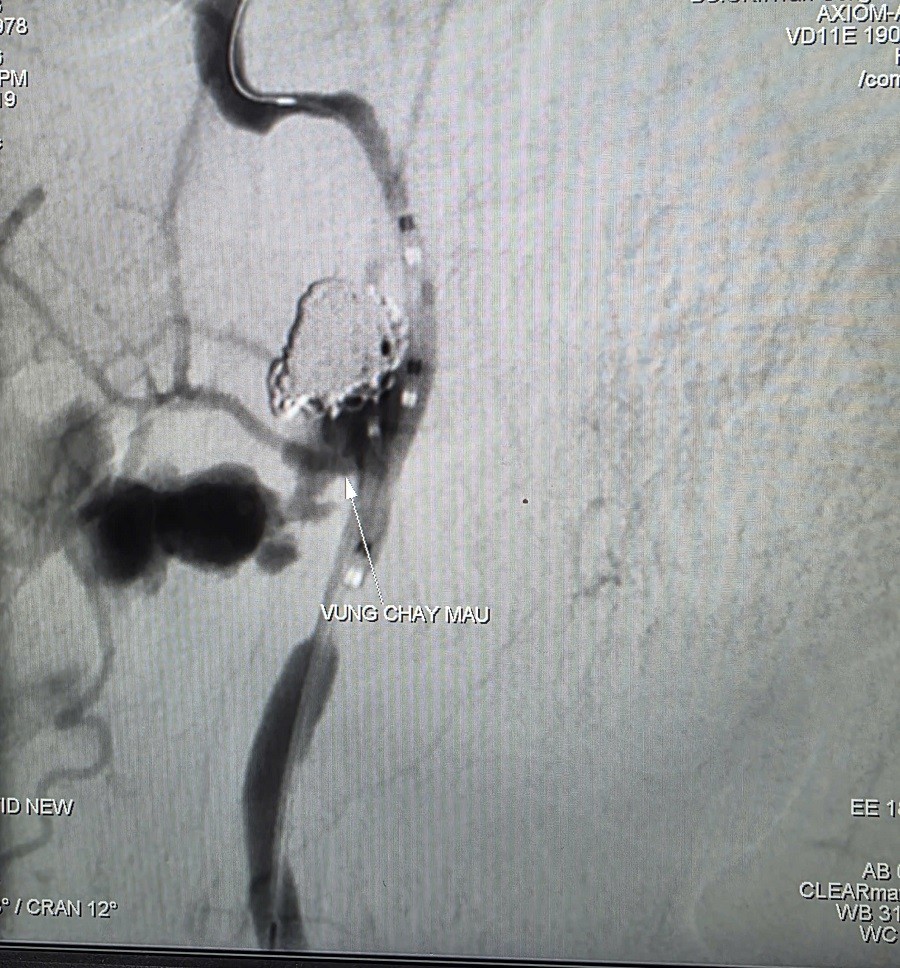

Hình ảnh thoát mạch trước can thệp

Kết quả CT Scan ghi nhận tổn thương vùng dạng khối choán chỗ khoang niêm mạc hầu lệch phải, xâm lấn vào động mạch cảnh trong tương ứng, có dấu hiệu thoát thuốc cản quang vào vùng hầu – họng cạnh bên và ổ giả phình động mạch cảnh trong đoạn dưới nền sọ.

Trước tình huống nguy kịch, nguy cơ mất máu ồ ạt, các bác sĩ quyết định thực hiện chụp và can thiệp cầm máu dưới mạch số hóa xóa nền (DSA). Thủ thuật do BS.CKII. Trần Công Khánh – Phó Trưởng khoa Chẩn đoán hình ảnh cùng ê-kíp thực hiện. Kết quả ghi nhận ổ giả phình động mạch cảnh trong phải đoạn cổ, dưới nền sọ, kích thước 4,2 x 4,8 mm, cổ túi phình rộng và đang chảy máu.